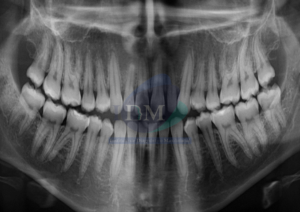

Caso 300 – IDM – HIPERPLASIA DE APÓFISIS CORONOIDES DE LADO DERECHO – IDM

Paciente femenino de 16 años acude al Instituto de Diagnóstico Maxilofacial (sede Miraflores) para evaluación quirúrgica. Radiografia Panorámica A la evaluación de la radiografía panorámica